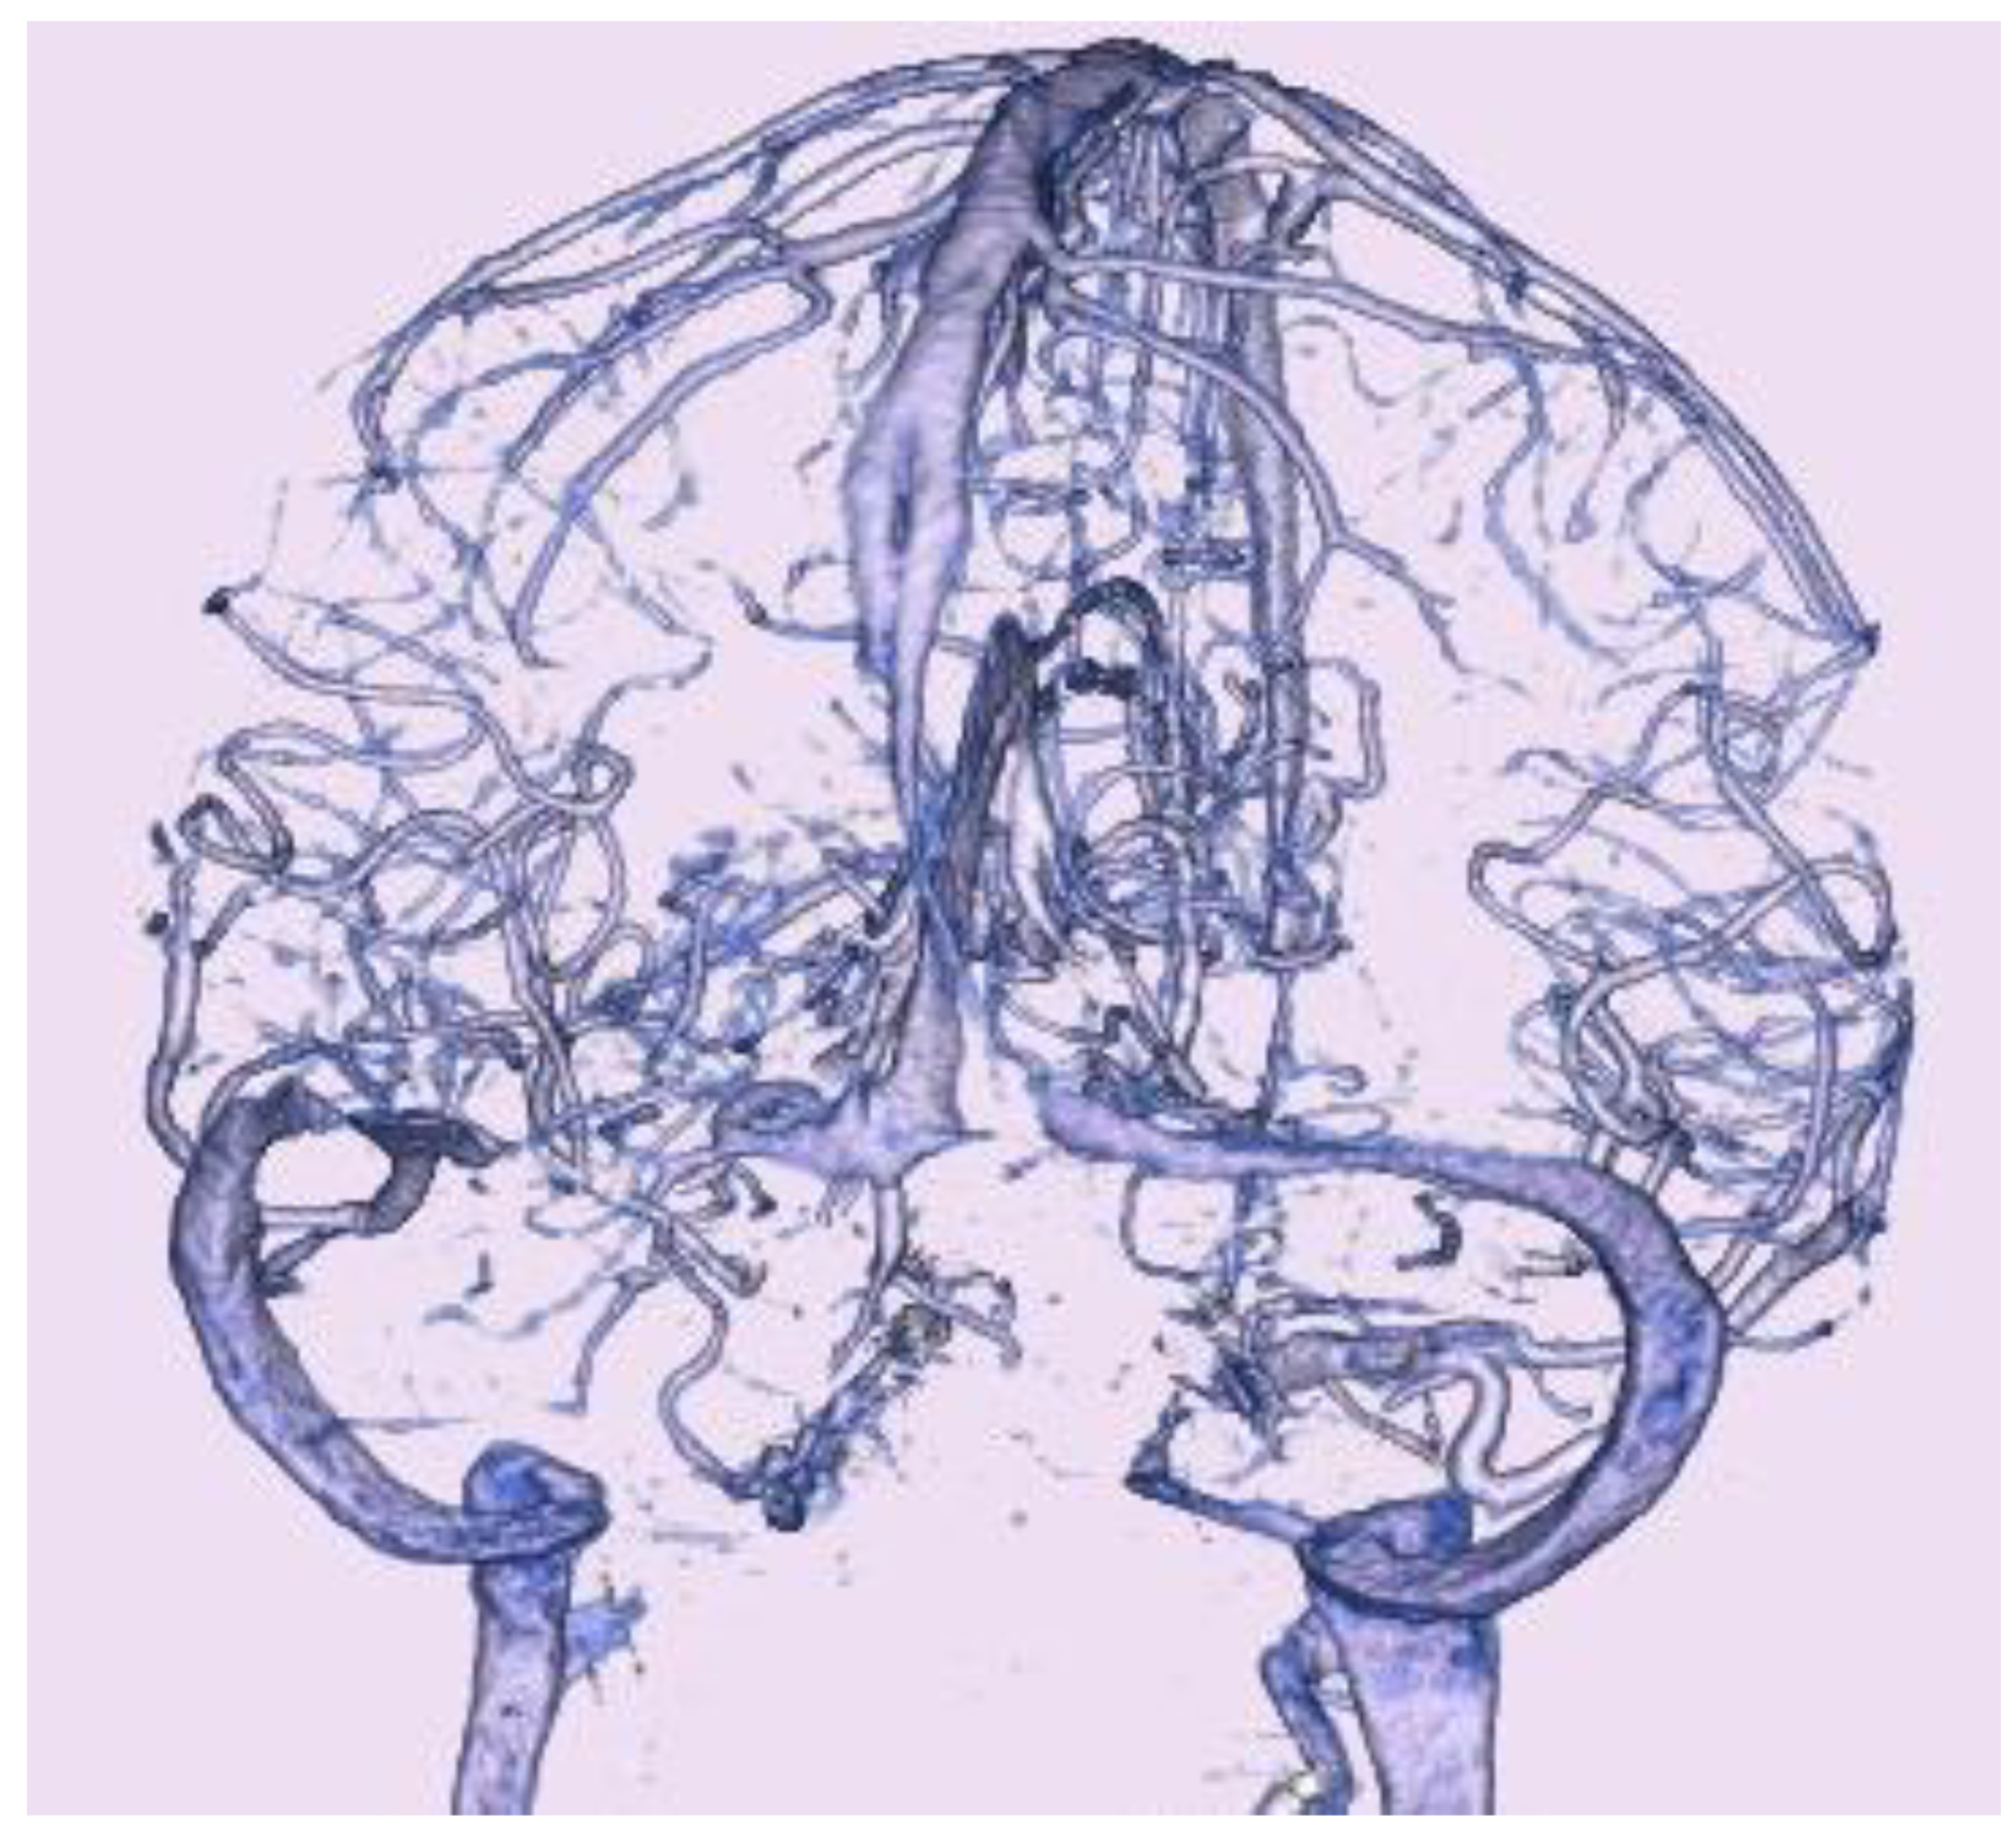

Computed tomography (CT) showed no acute hemorrhage. CT venography (Figure 3) showed bilateral stenosis of the transverse sinus, or bilateral dilatation of the adjoining vein of Labbe.

Figure 3. Computed tomography venography on admission. Computed tomography venography showed bilateral transverse sinus stenosis findings.